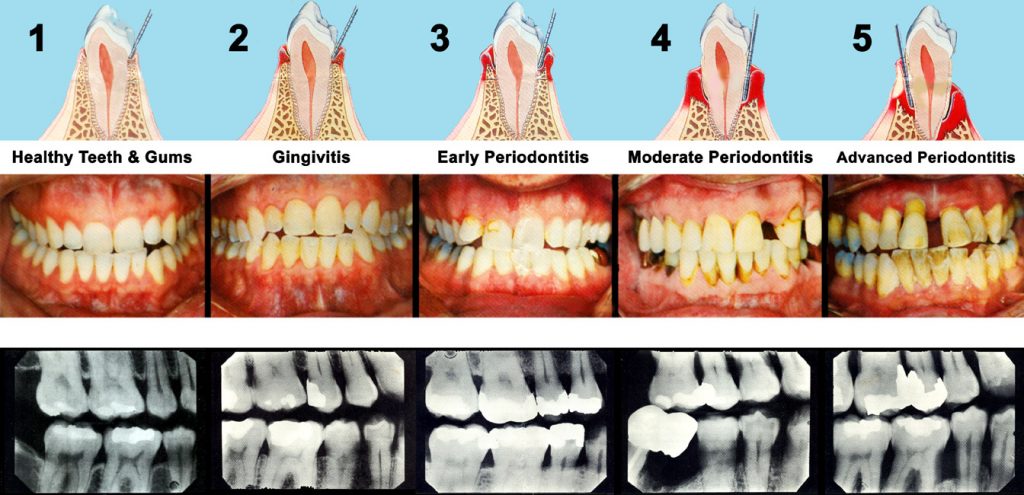

عفونت لثه دندان (Gum Infection) تحت تاثیر عوامل مختلفی مثل بیماریهای خاص، مصرف دارو، نقص سیستم ایمنی و…. ایجاد میشود و در صورتی که به موقع درمان نشود عفونت اولیه لثه یا ژنژیویت به مرحله شدید چرک لثه یعنی پریودنتیت تبدیل میشود که این اتفاق بسیار خطرناک است اما به کمک دندانپزشک متخصص پریو حرفهای قابل درمان است.

لثه های عفونی در مراحل اولیه ژنژیویت نام دارد که میتوان آن را با جرمگیری دندان و لثه کمک دندانپزشک متخصص حرفهای و توجه به رعایت نکات بهداشت دهان و دندان مثل استفاده منظم از مسواک، نخ دندان و دهانشویه و…. درمان کرد.

در صورتی که به ژنژیویت بیتوجه باشید و سریعا برای درمان آن اقدام نکنید عفونت اولیه لثه در زمان کوتاهی به بیماری پریودنتال لثه تبدیل میشود و پریودنتیت مرحله شدید و پیشرفته بیماری لثه است که درمان و بهبودی کامل آن بسیار سخت و زمانبرتر از درمان ژنژیویت است واگر به آن رسیدگی نشود منجر به از دست رفتن بافتها و استخوان پشتیبان دندان و تحلیل استخوان فک میشود.

در رابطه با تفاوتهای ژنژیویت و پریودنتیت همان طور که در webmd آمده است داریم:

Gingivitis (gum inflammation) usually happens before periodontitis (gum disease). But not all gingivitis leads to periodontitis. Most people get gingivitis at some point in their lives, and its mild symptoms make it easy to ignore. But without treatment, it can turn into bigger problems for your mouth. The good news is that you can prevent or even reverse it by simply brushing your teeth, flossing, and having regular dental cleanings and checkups.

معمولا زمانی افراد متوجه آن میشوند که دیگر خیلی دیر شده است و علائم جدی بروز کردهاند. عفونت و التهاب لثه به واسطه پلاک ایجاد میشود. پلاک لایه چسبنده باکتریها است که در روی سطح دندانهای ما تشکیل میشوند و ما ممکن است آن را به صورت جرم تغییر رنگ یافته مشاهده کنیم.